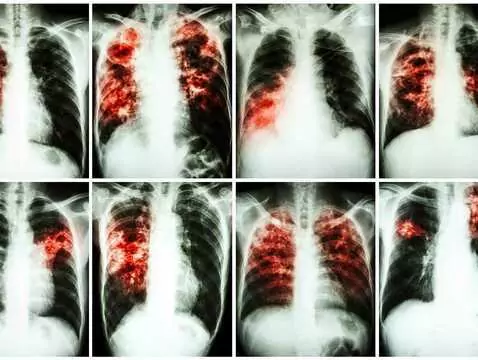

La tuberculose est une maladie qui n'a pas disparu. À l'occasion de la Journée mondiale de la tuberculose, il est bon de rappeler les informations les plus importantes sur cette maladie.

Il existe des maladies que l'on dit "éteintes" ou qui n'apparaissent que dans les pays dits du tiers-monde. C'est le cas de la tuberculose, considérée comme une maladie sporadique dans notre pays....

Des chercheurs de la faculté de médecine de Hradec Králové de l'université Charles de Prague ont inventé un nouveau médicament contre la tuberculose. Le médicament a été vendu à une société...